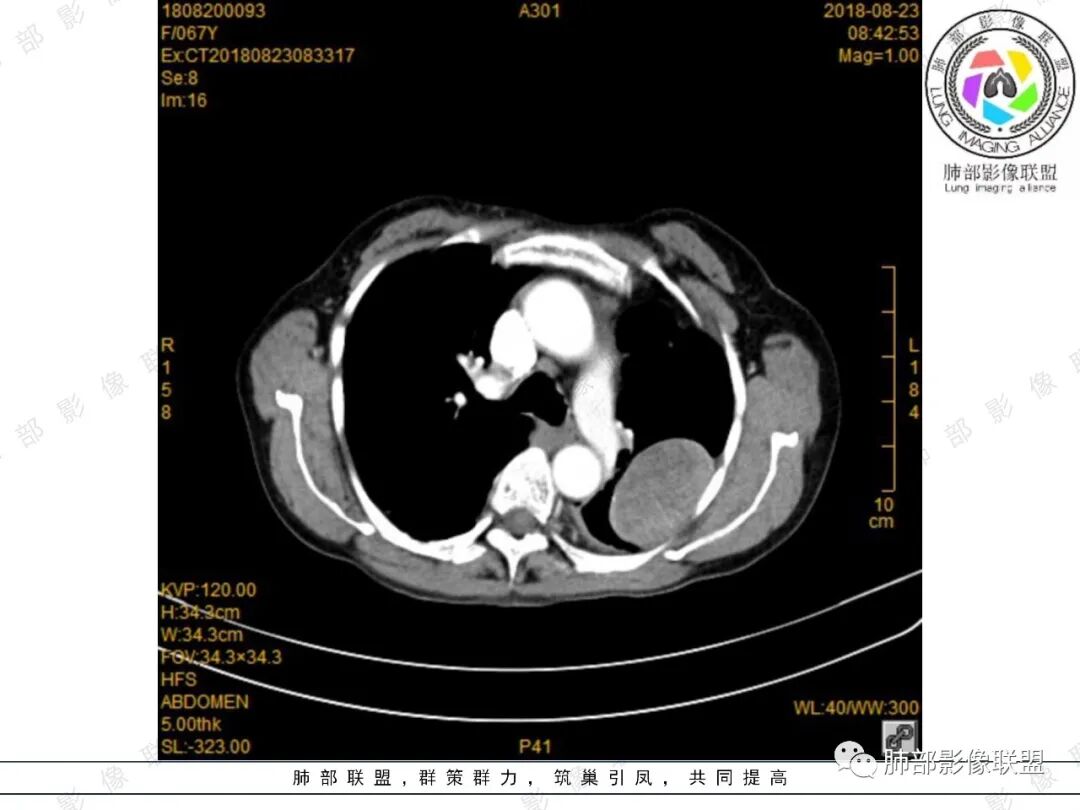

大雄:增强确实看的有些奇怪,胸部的无强化,脾内的轻度强化。如果是EMH,按理有强化的,除非全部脂肪变性了。虽然不是EMH好发位置,但也可以。淋巴瘤强化也不符合,胸部的这个形态也不太像淋巴瘤。如果只是单纯脾大,那么孤立的EMH也很少见。

看图说话:左肺肿块,边缘光滑,密度不均匀,不均匀强化,胸腔少量积液,纵隔肿大淋巴结。脾脏增大,见肿块影,不均匀强化,一元论,考虑淋巴瘤,转移瘤。

月亮圆了!:左肺上叶胸膜下肿块,宽基底与胸膜相连,边缘清晰,局部肺组织受压,支气管显示不佳,平扫密度不均匀,增强后,可见轻度不均匀强化,纵隔光滑,无分叶,无毛刺,周围组织无牵拉,收缩,内部有不均匀低密度,脾脏明显肿大,脾内多发类圆形低密度影,增强后,轻度强化,有便血,考虑可能:1:淋巴瘤2:脾梗死。

杨丽:老年女性,宽基底及胸膜掀起,考虑肺外病灶,供血动脉看不太不清,中等不均匀强化,首选sft;脾大,较均匀强化肿块,一元论考虑转移机会大,也不好除外二元论,淋巴瘤?

joyzhy:脾脏占位增大,特点延迟期强化和脾脏一致,考虑血管瘤。胸部占位,考虑肺外,鞘瘤或髓外造血。